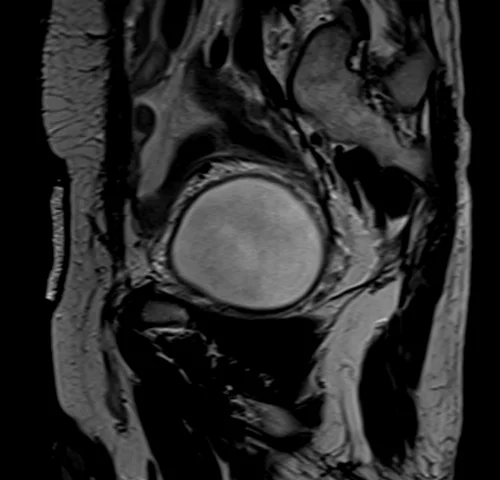

mri urinary bladder sagittal t2 image - MRI